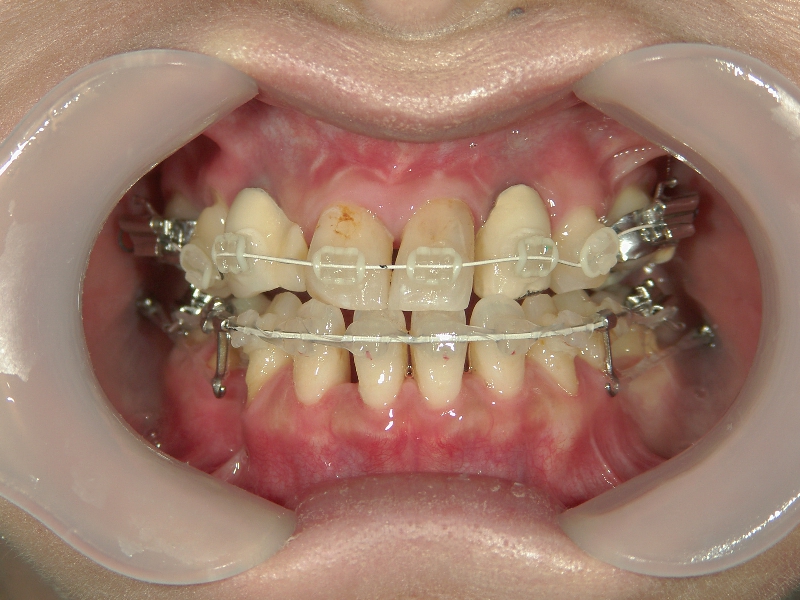

● ツインフォース

下顎が後退している方に用いられる装置です。後ろにずれている下顎を前方(本来の位置)に移動させ、噛み合わせを整えます。

上顎に比べ、下顎が著しく後退しています。

上の歯と下の歯を斜めに繋ぐようにツインフォースという装置を装着します。装置の力で、顎が前方へ押し出されてきました。